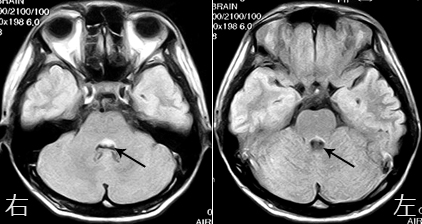

症例)27歳 女性 病歴)2週間くらい前から、右側を見ると物が二重に見える。眼科を受診したが眼球には異常所見ないと言われる。その後、総合病院脳神経外科を受診するが、頭部CT検査で異常所見ないと言われる。その後も症状持続するために当院受診となっています。

診察上、眼球運動障害があり、右側を見ると物が二重に見え、歩行も不安定でフラツキが強い状態でした。頭部MRI検査を施行すると、左のMRIに示すように矢印の部分が白く描出されています。そこが多発性硬化症をおこしている所見です。入院していただき、ステロイド治療を行うことで徐々に症状は改善しました。この疾患の難しいところは、一旦治療によって改善しても再発を繰り返すことです。そこが神経難病である由縁だと思われます。